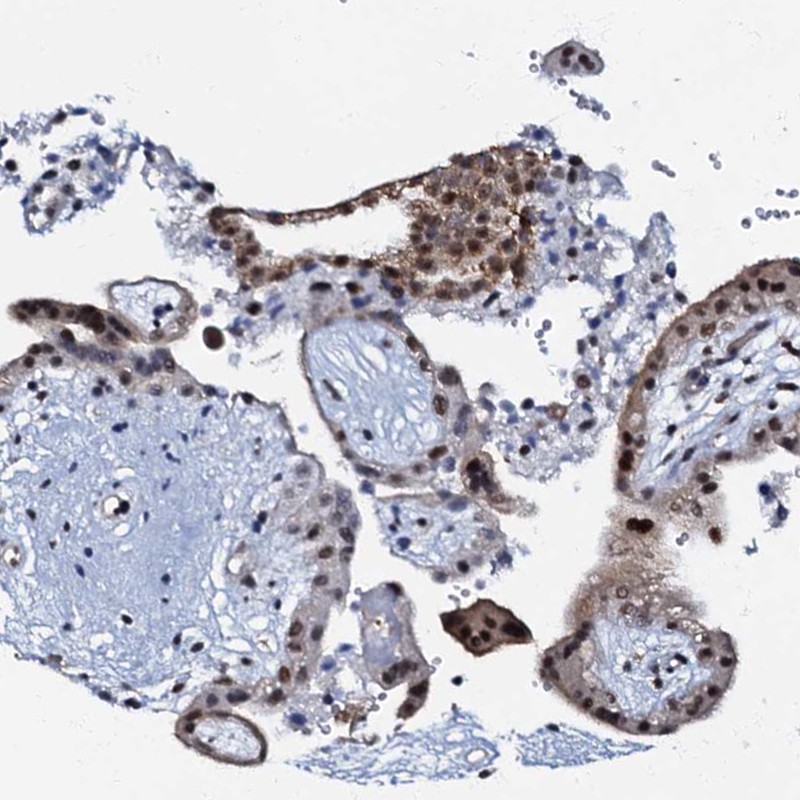

Immunohistochemical staining of human placenta shows nuclear positivity in trophoblastic cells.